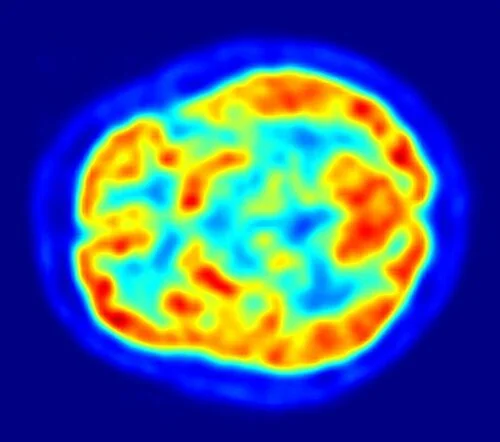

PET scans

PET scan of a healthy brain. Credit: By Jens Maus (http://jens-maus.de/) - Own work, Public Domain

• Like fMRI, positron emission tomography (PET) scans also show which regions of the brain are activated at any given time, but they use radioactive tracers such as radioactively labelled glucose.

• The radioactively labelled glucose will accumulate in parts of the brain which are respiring more and will produce a stronger signal on the PET scan.

• Just like MRI scans, PET scans have a high resolution and high quality.

• They can be used to determine the function of different brain regions and can also identify areas of brain damage or disease.